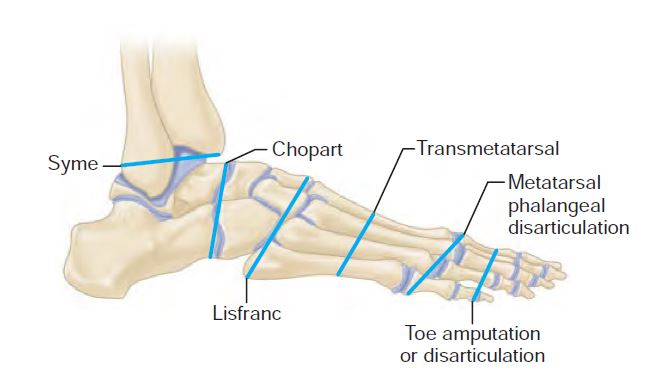

Анатомия суставов Шапарова и Лисфранка: фото и информация